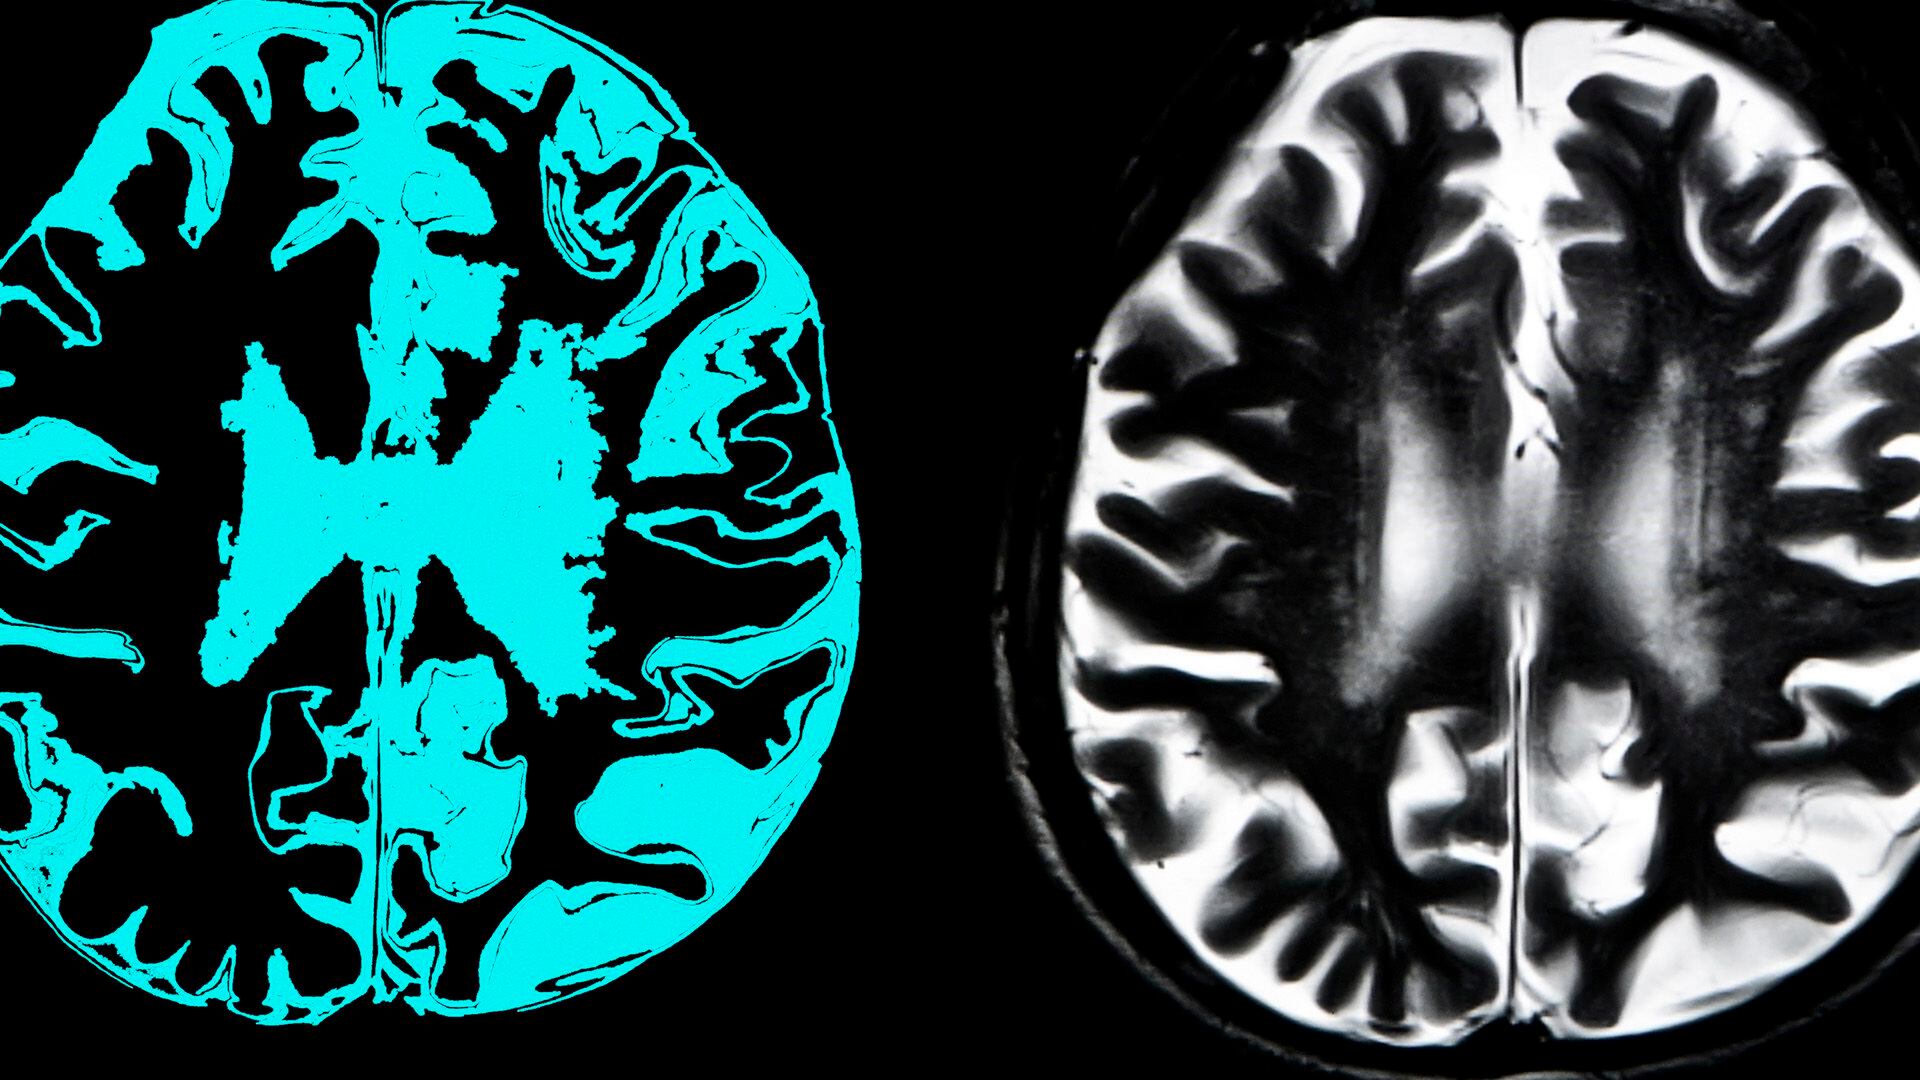

Cuando la enfermedad comienza a partir de los 70 años se caracteriza por una pérdida progresiva de la memoria reciente, con una atrofia del hipocampo, la zona del cerebro que nos permite aprender nueva información y recordarla.

Las causas del Alzheimer de inicio precoz se desconocen (a excepción de la genética), lo que sí se sabe es que no hay diferencias en cuanto a las alteraciones neuropatológicas que caracterizan la enfermedad: los depósitos de las proteínas beta-amiloide y tau en el cerebro.

Lo que sí puede cambiar en personas con presentaciones atípicas, sobre todo durante la fase inicial de la enfermedad, son los patrones de la distribución en el cerebro de la proteína tau, que son “un poco diferentes”, destacó Grau.